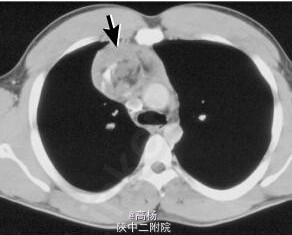

查体:口唇发绀,呼吸急促,吸气相呈轻度三凹症,右侧胸廓饱满,呼吸活动度减弱,听诊呼吸音减轻,叩诊呈实音,心音中,律齐。 辅查:胸片:右侧肺野密度增高影。CT:右侧胸腔混杂密度软组织肿块。如图。

诊断:右纵膈畸胎瘤 处理:予半高卧位,辅以吸氧、雾化、止咳等对症支持治疗。于全麻下行肿块切除术,选择右前外侧第六肋间切口进胸,膨肺探查右肺组织发育良好。术后称量肿瘤实性组织1.15kg。术后病理:肿瘤囊、实性共存,由成片皮肤、肠管、软骨、骨、神经组织及纤维脂肪组织构成。局部见少量实质尚未成熟的神经组织及腺管,但未见内胚窦,病理科建议可不予化疗,常规随访。术后予补液、营养支持等对症处理,病情稳定后出院。